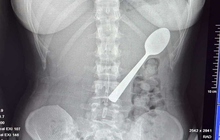

img

Chiếc thìa trong cơ thể của người phụ nữ.